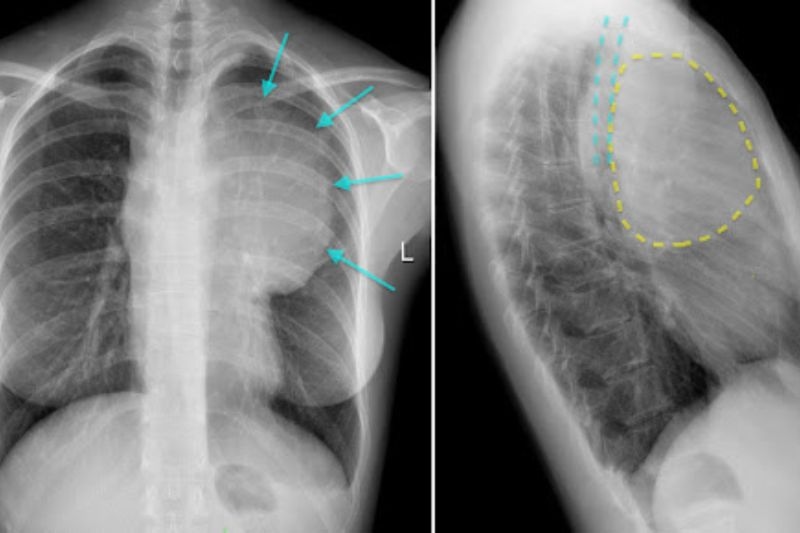

Ngoài ra, ở tư thế nghiêng, trung thất còn được chia thành ba vùng: trung thất trước, giữa và sau. Việc phân vùng này giúp bác sĩ định hướng chính xác hơn nguồn gốc khối u.

2. Chẩn đoán hình ảnh X quang u trung thất diện nghiên

2.1. Trung thất trước

Phần trung thất trước được giới hạn phía trước bởi xương ức và phía sau bởi mặt trước tim. Ở trẻ nhỏ, khu vực này chứa nhiều mô tuyến ức, cơ quan đóng vai trò miễn dịch, nhưng theo thời gian tuyến ức dần teo lại và để lại khoảng trống. Chính không gian này có thể trở thành vị trí hình thành khối u.

2.2. Trung thất giữa

Vùng này nằm ngay sau trung thất trước, kéo dài đến khoảng 1cm trước mặt trước cột sống. Đây là khu vực chứa nhiều cấu trúc quan trọng như tim, khí quản, mạch máu lớn, vì vậy khối u xuất hiện tại đây có thể gây ra nhiều triệu chứng rõ rệt hơn.

2.3. Trung thất sau

Trung thất sau nằm sát cột sống và chứa nhiều cấu trúc quan trọng như động mạch chủ xuống, tĩnh mạch đơn, hệ thần kinh giao cảm. Đây là khu vực mà trẻ em thường gặp khối u hơn so với người lớn.